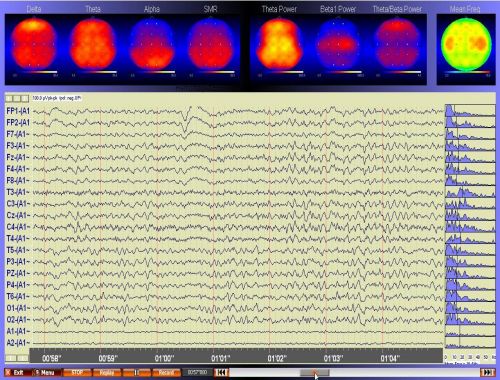

QEEG steht für „Quantitative Elektroenzephalografie“. Hierbei wird das EEG während einer Ruhebedingung und während verschiedener Leistungssituationen gemessen. Das EEG wird dann mit den Werten einer gesunden Normpopulation verglichen, wodurch eine gesicherte Diagnosestellung ermöglicht wird. Das QEEG stellt somit ein Assessment-Tool dar.

Die Abbildung zeigt die Aufzeichnung eines QEEGs. Im unteren Teil des Fensters sind die Original-EEG-Wellen der Ableitorte nach dem 10-20 System zu sehen. Im oberen Bereich kann -in Echtzeit- der Erregungszustand des Gehirns (hier bezogen auf bestimmte Wellenbereiche) direkt beobachtet werden. Es kann sofort gesehen werden, wie das Gehirn auf bestimmte Anforderungen (z.B. Ruhe oder Leistung) reagiert.